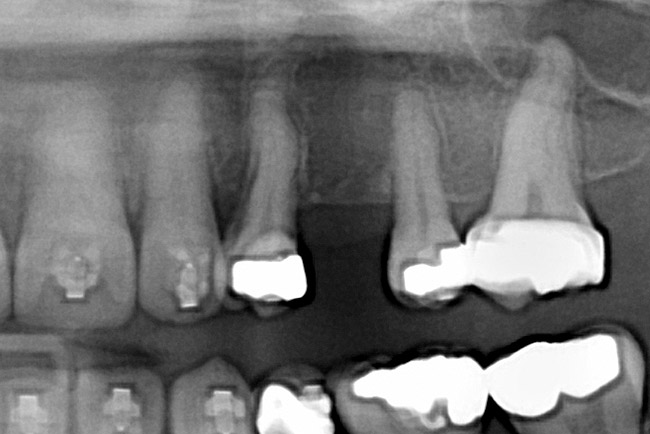

Fig 11. Corticotomy SFOT. A 42-year-old male presented with a history of extraction orthodontic therapy.

Figure 11

Fig 12 (and Fig 13). Incisors were too upright and had severe incisal wear. He was concerned about esthetics of the worn teeth and his insufficient lip support. Progress photo and panorex 9 months after corticotomies were performed on Nos. 6 through 11. Previous extraction sites were reopened orthodontically to improve function and fill lip support. Incisal edges were restored provisionally with composite resin. Note that despite the creation of adequate spaces to replace missing teeth, there is inadequate room for placement of dental implants because of severe tipping of all the anterior teeth. Osteotomy SFOT may have been a better choice because it would have allowed needed alveoloskeletal correction (without excessive tipping) instead of the primarily dentoalveolar correction common in corticotomy SFOT. Restorative dentist: Brad Jones, DDS.

Fig 13 (and Fig 12). Incisors were too upright and had severe incisal wear. He was concerned about esthetics of the worn teeth and his insufficient lip support. Progress photo and panorex 9 months after corticotomies were performed on Nos. 6 through 11.